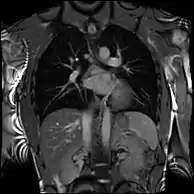

Partial Anomalous Pulmonary Venous Drainage by CMR

Enlarged right ventricle with poor function in a patient with repaired tetralogy of Fallot by CMR